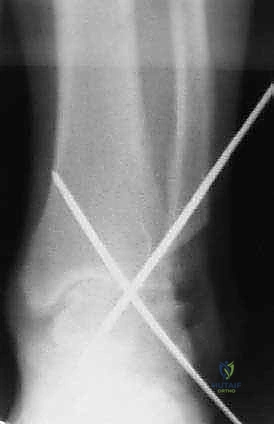

- التثبيت الصلب (Rigid Fixation): يتم تثبيت العظام في وضعيتها الجديدة باستخدام مسامير طبية كبيرة مجوفة (Cannulated Screws) مصنوعة من التيتانيوم. يتم إدخال هذه المسامير عبر العظام بتقنية متقاطعة لضمان أقصى درجات الثبات والضغط بين السطحين العظميين.